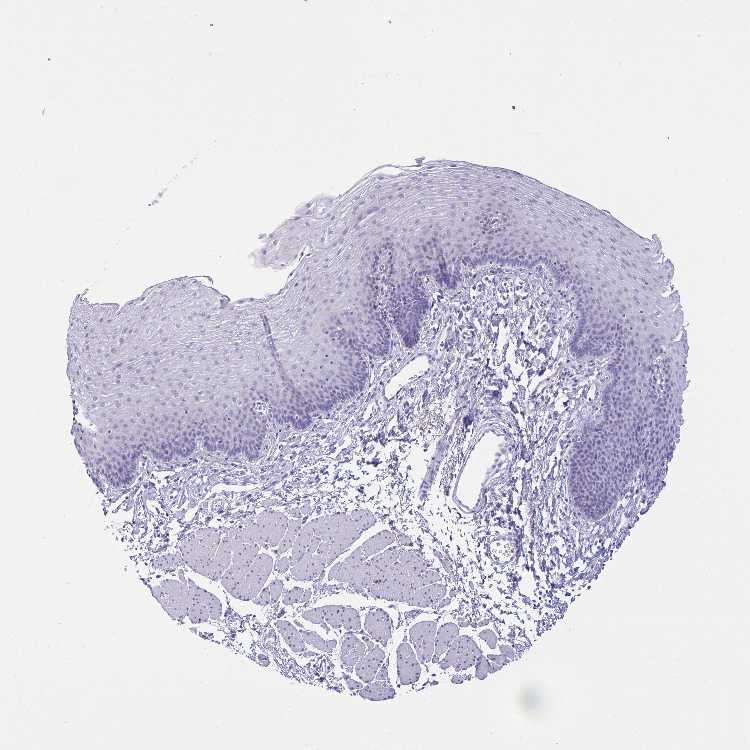

ESOPHAGUS - Antibody stainingi

Antibody staining in the annotated cell types in the current human tissue is reported as not detected, low, medium, or high, based on conventional immunohistochemistry profiling in selected tissues. This score is based on the combination of the staining intensity and fraction of stained cells.

Each image is clickable and will lead to virtual microscopy that enables deeper exploration of all samples and also displays staining intensity scores, fraction scores and subcellular localization as well as patient and tissue information for each sample.

Antibody HPA053752Antibody HPA058032

Squamous epithelial cells Not detectedNot detected